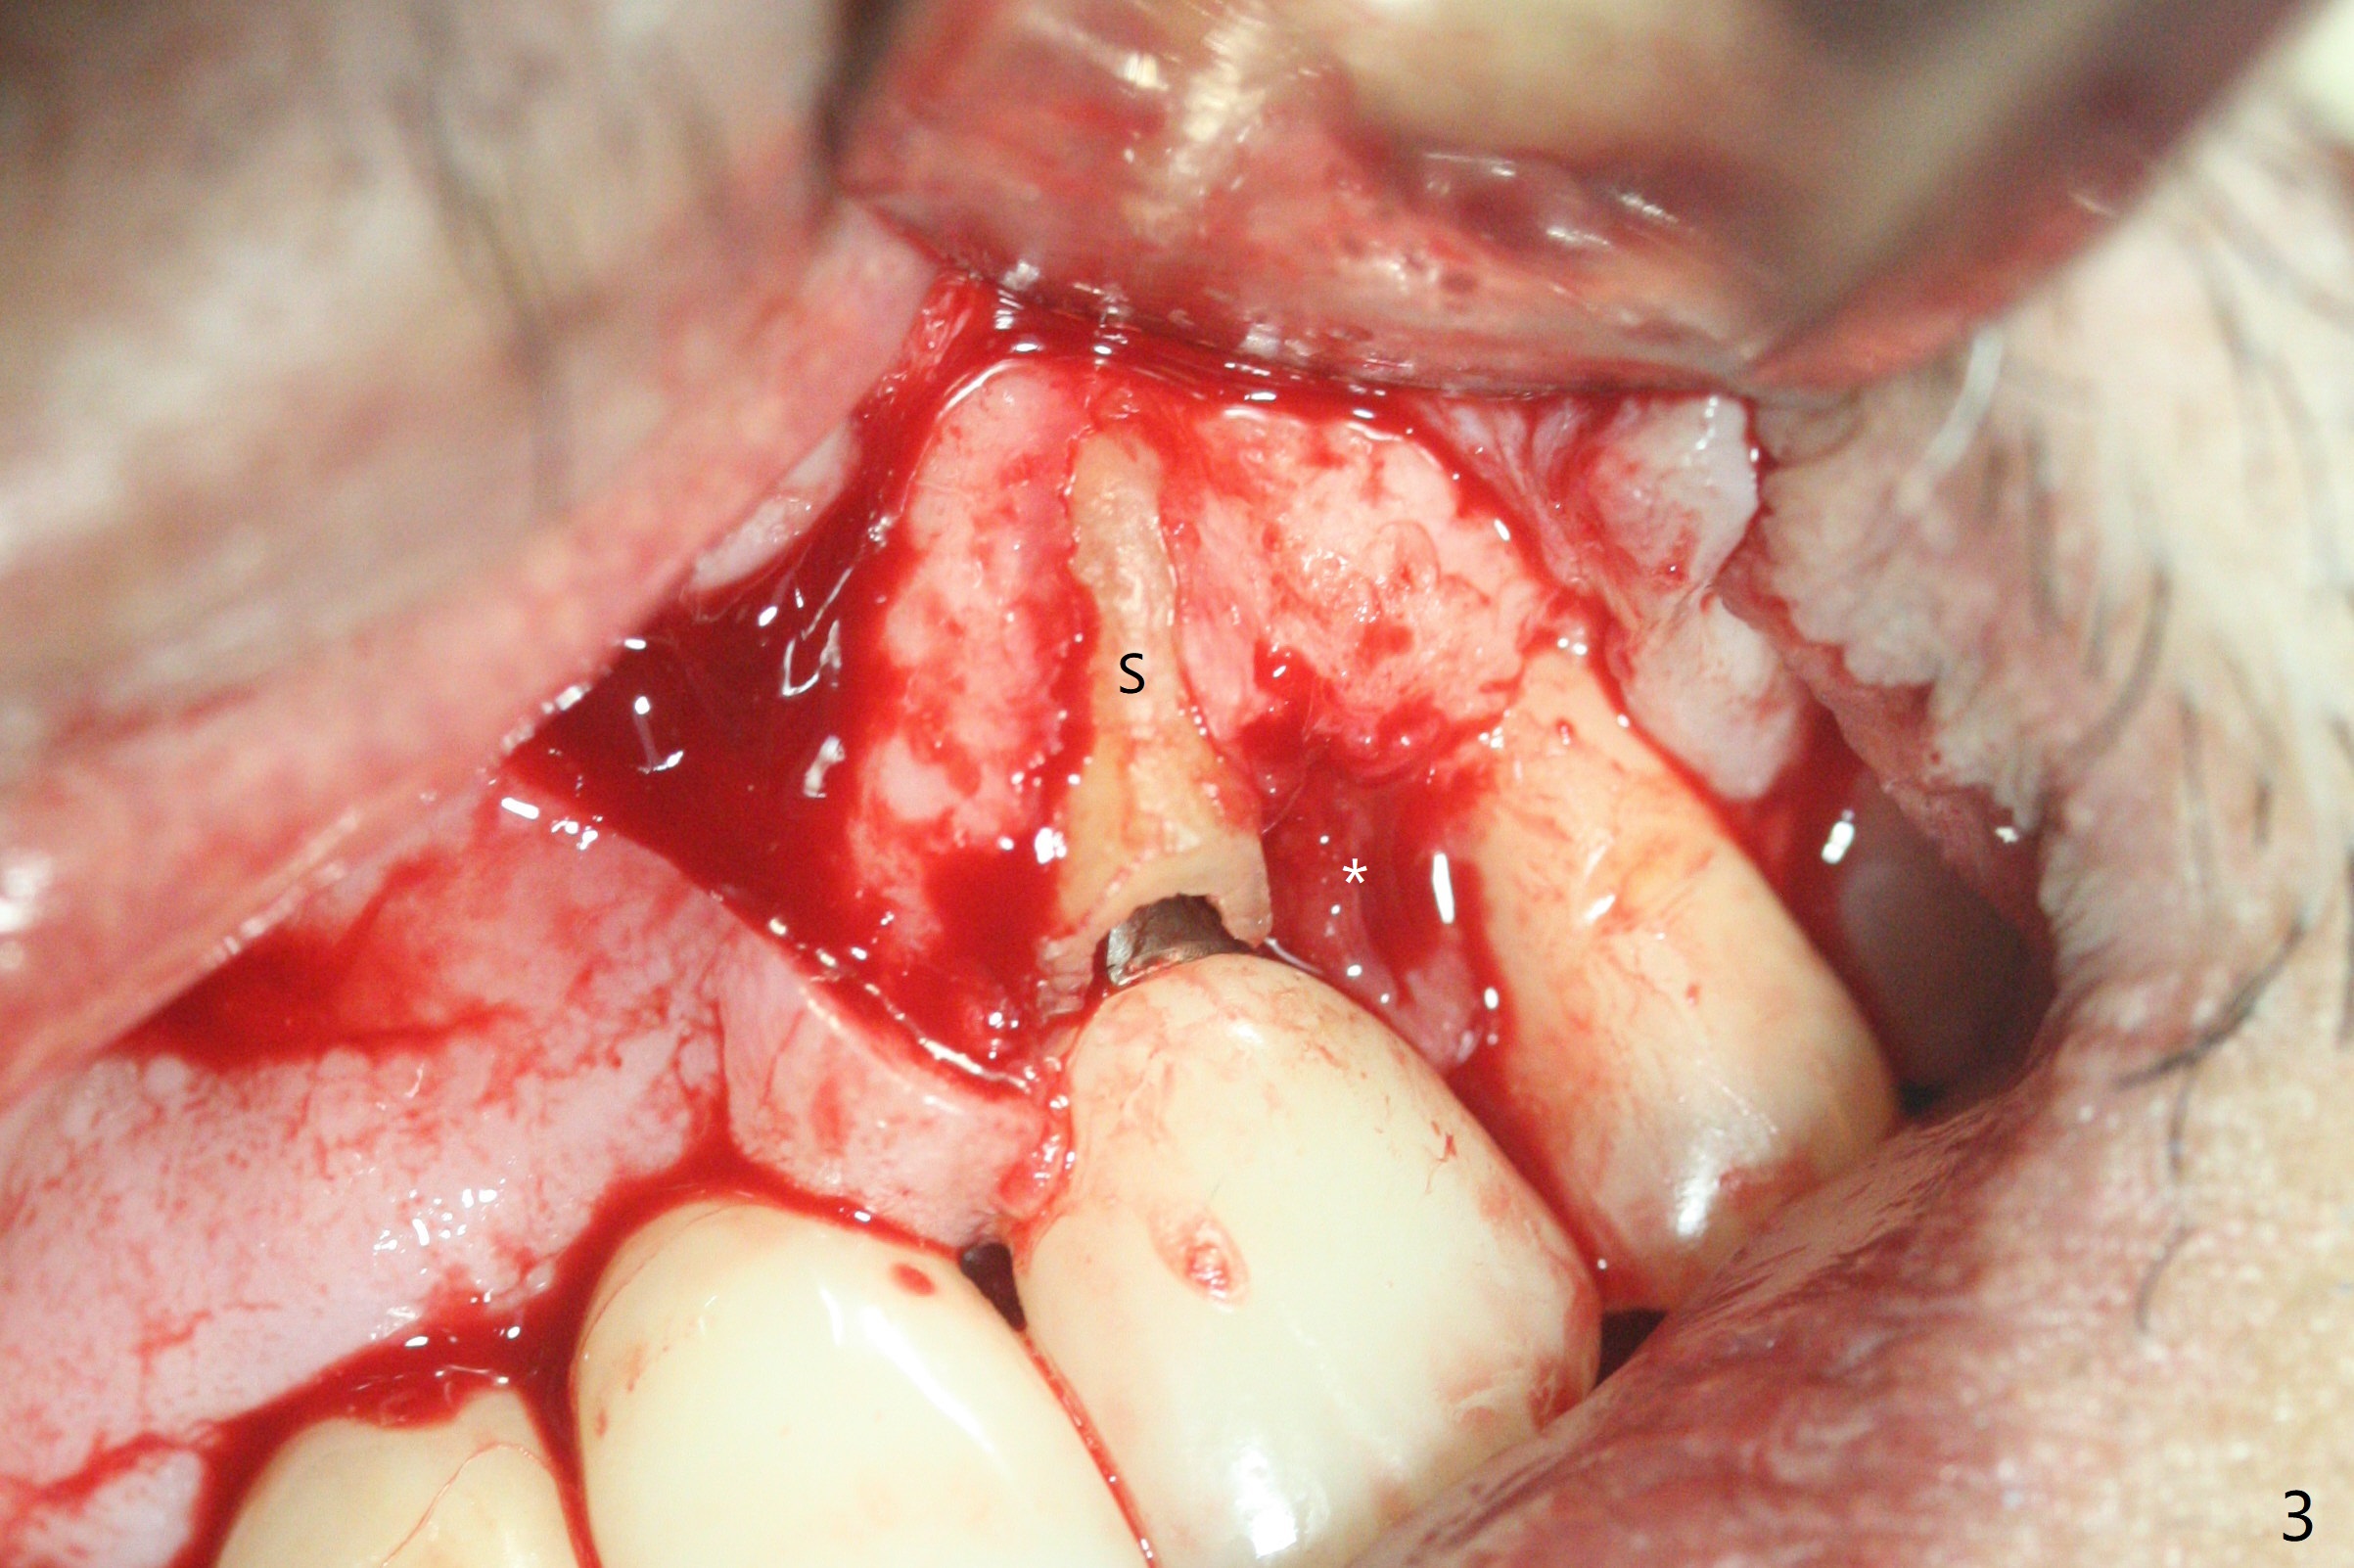

There is no obvious black triangle between the implants at #8-11 (Fig.1 post infiltration). Following papilla (Fig.2 *) sparing incision and elevation of the buccal flap, the fenetration of the buccal plate around the socket shield (Fig.3 S) is found at #11; there is a distal defect with granulation tissue (*). After shield and granulation tissue removal, the coronal implant is found exposed (Fig.4 until osteotomy). The relatively flat surface of IBS implant is apparently less likely to develop periimplantitis. With periosteal relief and placement of sticky bone (Fig.7 *), PRF and 6-month membrane, the wound is closed with 4-0 PTFE suture (Fig.5). Failure of socket shield is related to retention of the apex (Fig.6 <). Probe before extraction and remove apex and gutta percha. There appears no buccal or palatal (P) defect 9 months post shield removal (17 months post cementation, Fig.8), although the bone density palatally is low. Although the sagittal section (Fig.9 (lower left panel) shows the absent palatal plate at #10, the 3-D image and the coronal section do not (upper let and right panels). The 2.5 mm implant at #9 appears to have been placed buccal (Fig.10 B), although the buccal crest is present. In contrast the 2.5 mm implant at #8 appears within the bone boundary (Fig.11). The soft tissue remains healthy at #8-11. Bone graft will be done if needed.